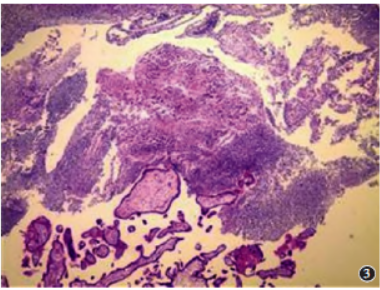

手术及病理:全麻行腹腔镜手术探查,探查盆腔少量淡血性液体积聚,可及瘢痕子宫,周围粘连明显,双侧输卵管、卵巢未见明显异常。向头侧探查可及肝S5有一直径5cm囊性肿物,肝脏色泽正常,周围粘连,结合术前HCG升高,术中考虑肝脏妊娠。完整切除孕囊后,电凝止血肝脏创面。术后剖验标本见孕囊内死胎,

图3病理图示切除组织光镜下见绒毛组织(HE×100)